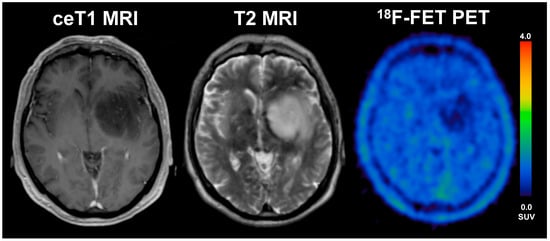

Figure 4.

57-year old female with glioblastoma (WHO grade IV, IDH wildtype, MGMT unmethylated) and an overall survival of 4.9 months (STS). The diameter of CE on T1 MRI was 31 mm, the volume of CE was 6 mL, the BTV in FET-PET was 39.1 mL, the TTPmin was 12.5 min and TBRmax was 3.9. The patient underwent radiochemotherapy.